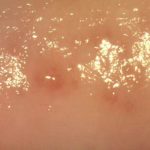

Герпес на половых губах (фото 2) на начальном этапе проявляется покраснением и пузырьками, которые созревают в течение 5-7 дней, а потом лопаются. Выглядит герпес на половых губах в виде скопления пузырьков, которые могут собираться в группы, либо появляются вразброс на поверхности кожи. Окружность пузырьков имеет ровные границы, кожа по краям гиперемирована.

На слизистых оболочках герпес увидеть очень легко, поскольку место возникновения будущих пузырьков не только болит и чешется, но и краснеет. Так герпес входа влагалища характеризуется ярко-красными пятнами, в центре которых можно заметить пузырьки с прозрачной жидкостью. Герпес на клиторе имеет подобные симптомы. Края герпетических высыпаний ровные, герпес в интимной зоне у женщин крупными пузырьками не отличается.